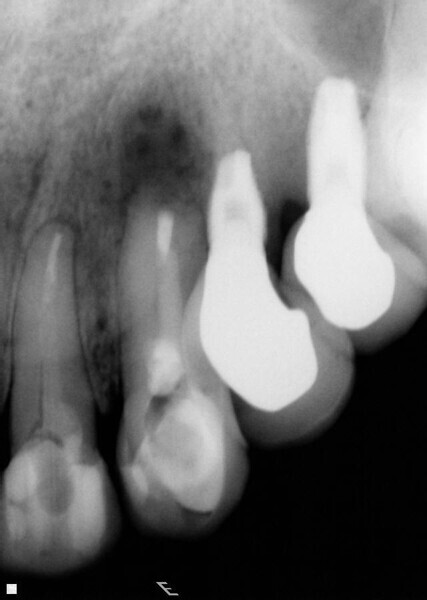

Fig. 4: Periapical radiograph during the root-end surgery verifying the complete root-end filling.